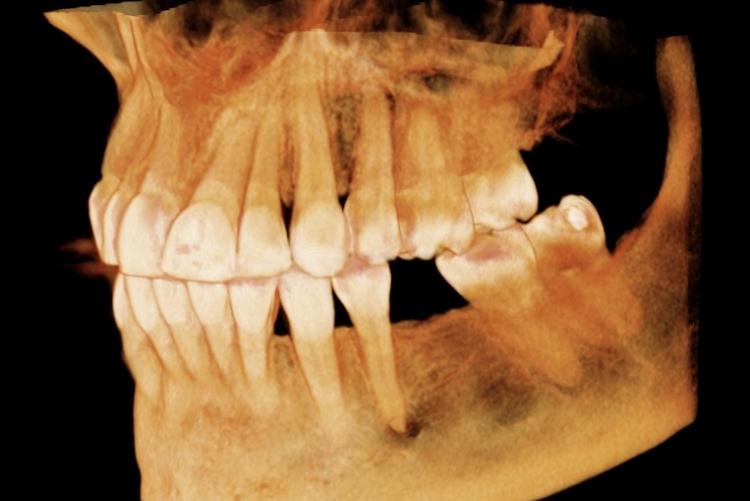

Conventional intra-oral radiography provides clinicians with cost-effective, high-resolution imaging that continues to be the front-line method for dental imaging. However, it is clear that there are many specific situations where the 3-D images produced by CBCT facilitates diagnosis and influences treatment. The usefulness of the CBCT cannot be disputed. It is a valuable task-specific imaging modality, producing minimal radiation exposure to the patient and providing maximal information to the clinician.